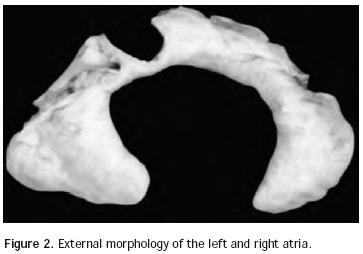

Atrial situs: In normal conditions there are two anatomically well–differentiated atria in both cardiac antimers that, as it was previously stated, are morphologically and functionally asymmetric. The right atrium has two essential anatomic features: the triangular shape of its appendix, with a wide base incorporated to the atrial cavity showing the inner cresta terminalis and the pecti–neus muscles. On the other hand, the left atrium is also characterized as such due to the shape of its appendix, which shows an elongated configuration in the form of a glove finger with a narrow base, which is not incorporated to the atrial cavity (Figure 2). The right atrium receives the superior caval vein and the inferior caval vein, which seem to pull it longitudinally, thus giving it an elongated appearance. Conversely, the left atrium receives the four pulmonary veins that seem to pull it transversally, thus giving it a widened appearance.